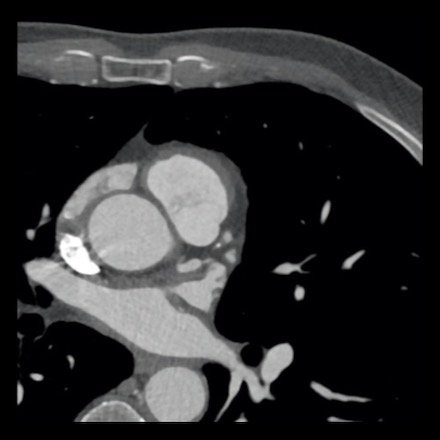

case 2 – CAD-RADS 5/P2/S

First, scroll through the CTA images.

How would you describe the findings on the coronary CTA?

The findings are:

- Stent in the mid

LAD with low-attenuation within the stent suggestive of minimal in-stent

restenosis (<25%). Non-calcified plaque distal to the stent

causing mild stenosis (25-49%). Notice bridging on a short segment in

the distal LAD. - Non-calcified

plaque in the LCX causing mild stenosis (25-49%). - Occlusion of the

proximal OM1 branch with distal filling. - Calcified and

non-calcified plaques in the proximal RCA causing mild (25-49%) stenosis. - Total plaque burden

is moderate based on SIS (four segments including proximal RCA, mid LAD, prox

LCX and OM1).

Due to the occlusion of OM1 branch and presence of the stent, this case

reads as CAD-RADS 5/P2/S, which means that this patient needs further

diagnostic workup.